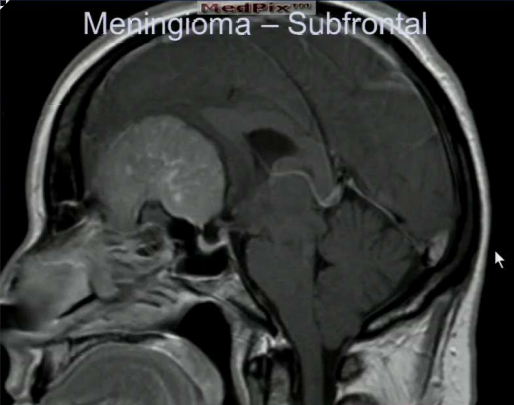

What is the most common place to find a huge meningioma?

Frontal cortex. This will not present with clinical symptoms until it gets large, compared to the temporal cortex which only needs a small tumor to cause clinical symptoms.